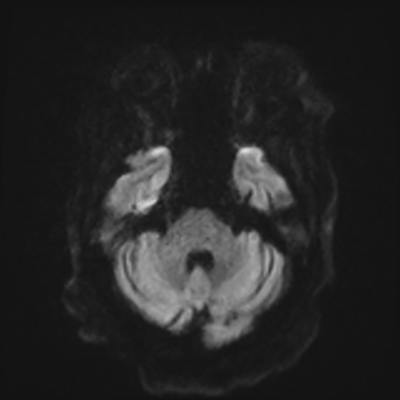

You come back the next day and see how things are going. The patient's electrographic record has shown a moderate encephalopathy (diffuse slowing, disorganization) with frequent right posterior quadrant delta slowing. Based on this result, and an adequately improved clinical examination, you give the okay to proceed with obtaining an MRI of his brain. This is shown below.

MRI brain (DWI)